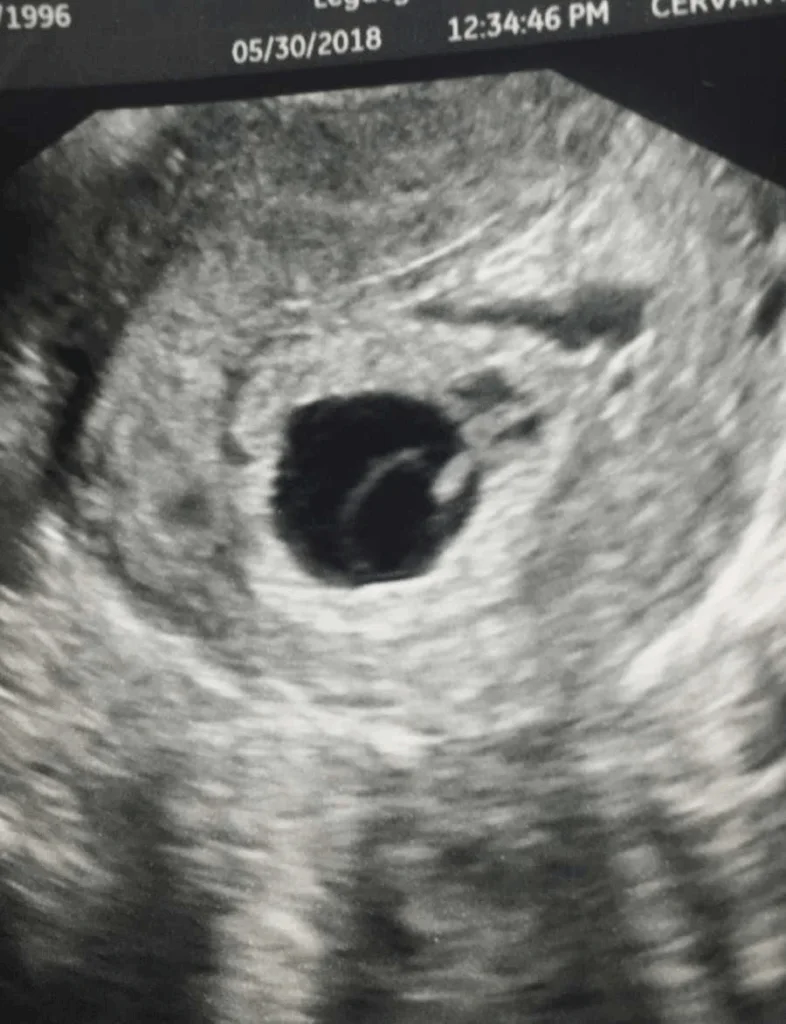

Back to the ultrasound table she went, her heart pounding this time for a different reason. Fear and hope clashed in her chest. Maybe it was a twin, maybe an ectopic pregnancy, maybe something else entirely. The transvaginal ultrasound revealed what the first one had missed. There was a baby. About six weeks along. But there was no heartbeat.